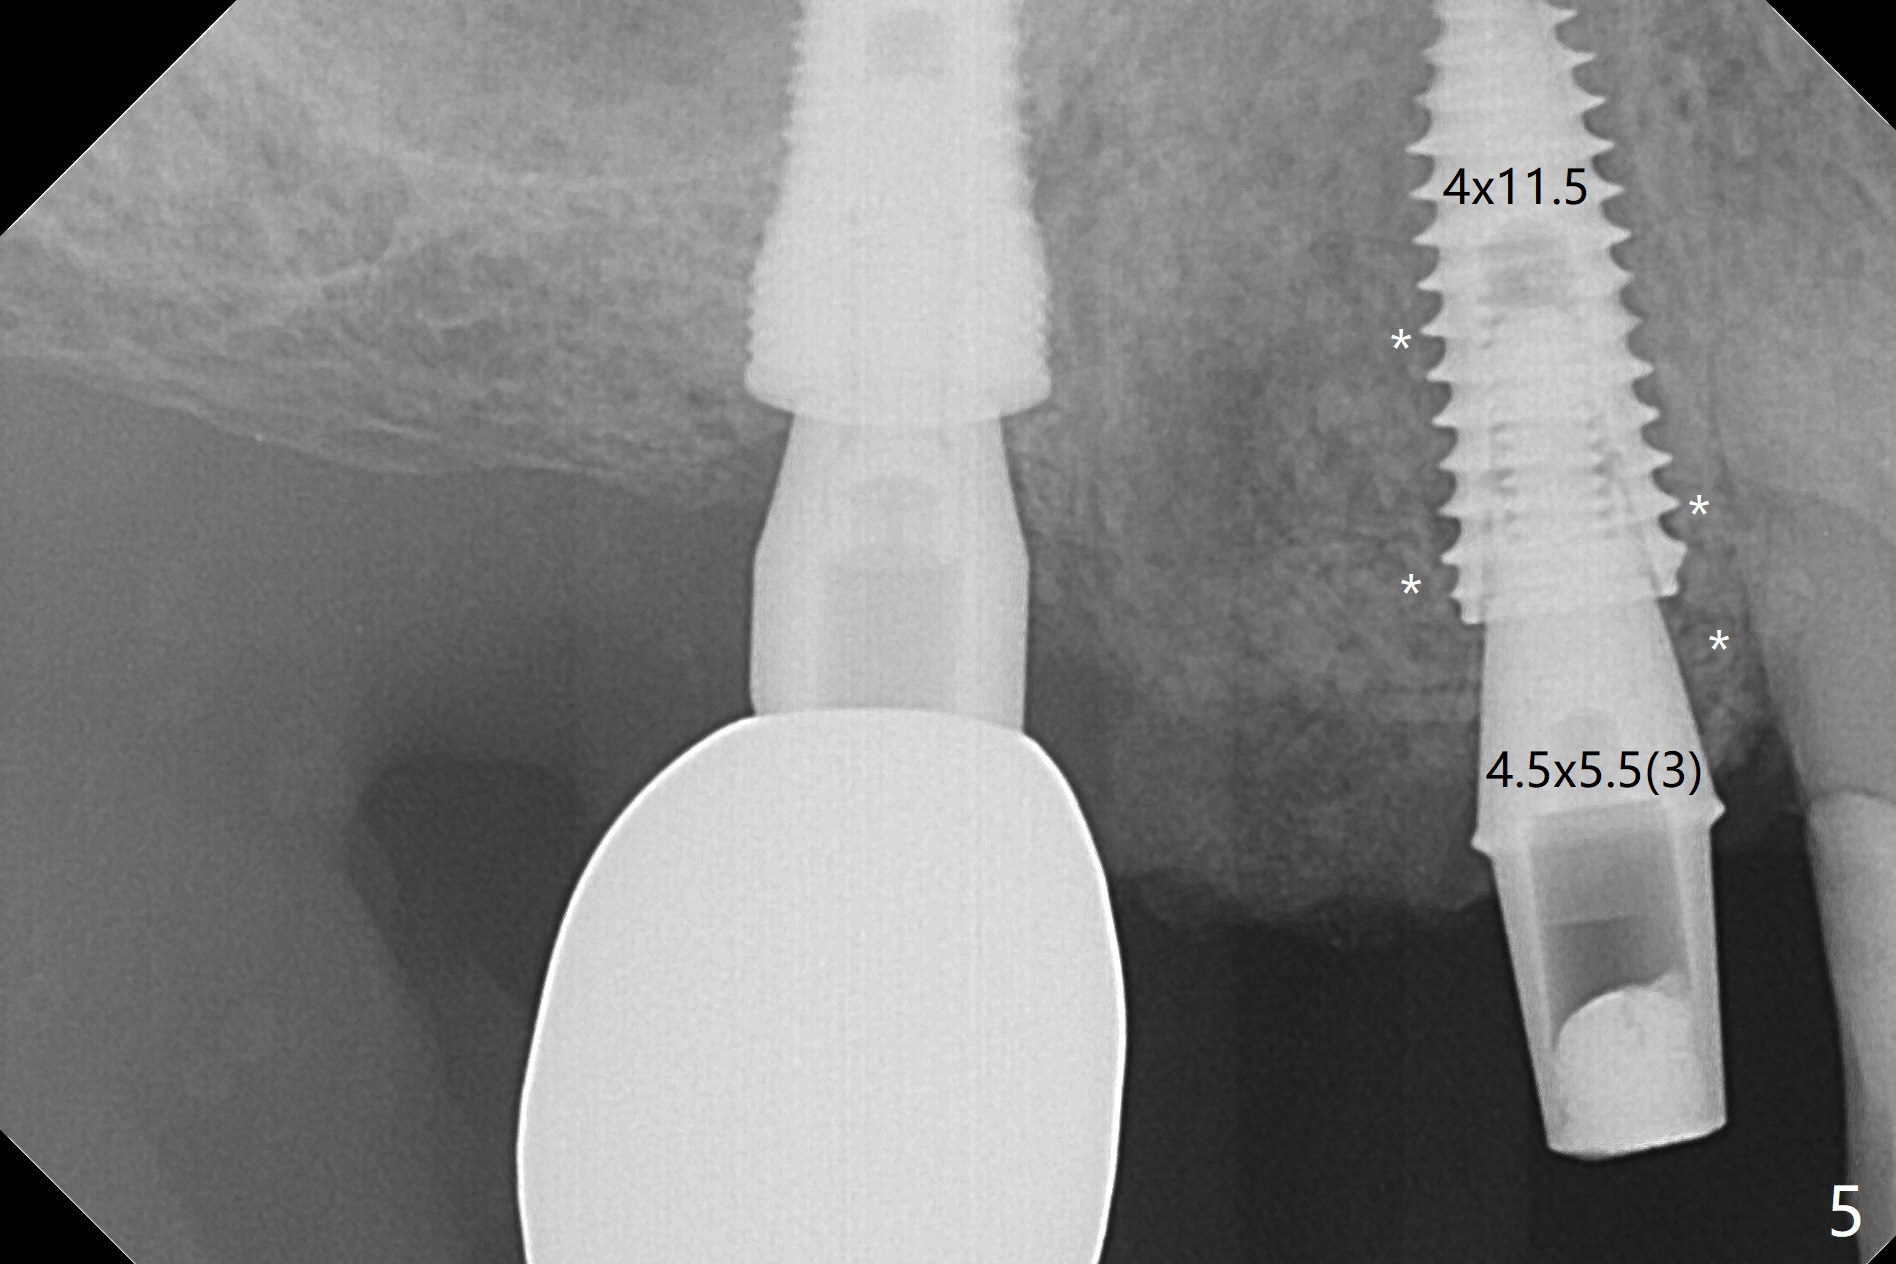

Today schedule is to extract the teeth #4 and 5 and place an implant at #5. When the latter is done, it appears that the implant at #15 should be placed at the same appointment (Fig.1). Once an abutment is placed at #5 (Fig.2 A, 5) for temporary crown (Fig.4 T) , the guide may be not seated again unless the crown is removed. Luckily the implant placement at #15 is quick and smooth with the guide (Fig.3,6). The implants seem to be covered by the bone 4 months postop (Fig.7,8). #15 abutment screw needs retightening because of long crown 1.5 months post cementation. Access hole is palatal. There is premature contact in lateral movement. The buccolingual occlusal table is large at #14 and 15. In fact there is more occlusal contact at #14 than #15 in centric occlusion. Tissue level implants should have been placed to reduce implant/abutment loosening. The incomplete abutment seating (Fig.5,7) is noted after retightening the loose cantilever FPD 1 year post cementation (Fig.9 <). After removal of the FPD, the abutment is reseated completely without interference of the proximal contacts (Fig.10).